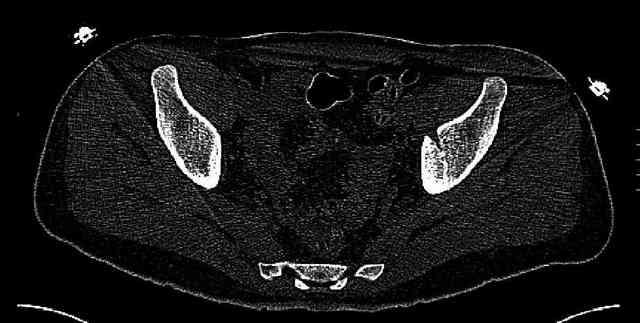

The joint is non-concentric as the head appears to be either "following the caudal segment", or the dome component is displaced from the tethered head... or so it seems... and he's young... so, many fracture surgeons would recommend reduction and fixation.

So we must decide preoperatively which part is the displaced segment?

It's difficult to know from these few selected images which component of the injury (was before and now) should be deemed the "soon to be mobile"

segment. It's my best guess that it is the caudal portion and there exists a healing fracture line somewhere thru the posterior column...one image

suggests it. If true, its early healing/union should be disrupted, and the resultant fragment mobility then allows accurate reduction.

Some more images. Does it help to guess which part of the acetabulum is displaced?

Normal appearing SI joints and a healed posterior column limb... my bet's on caudal segment displacement.